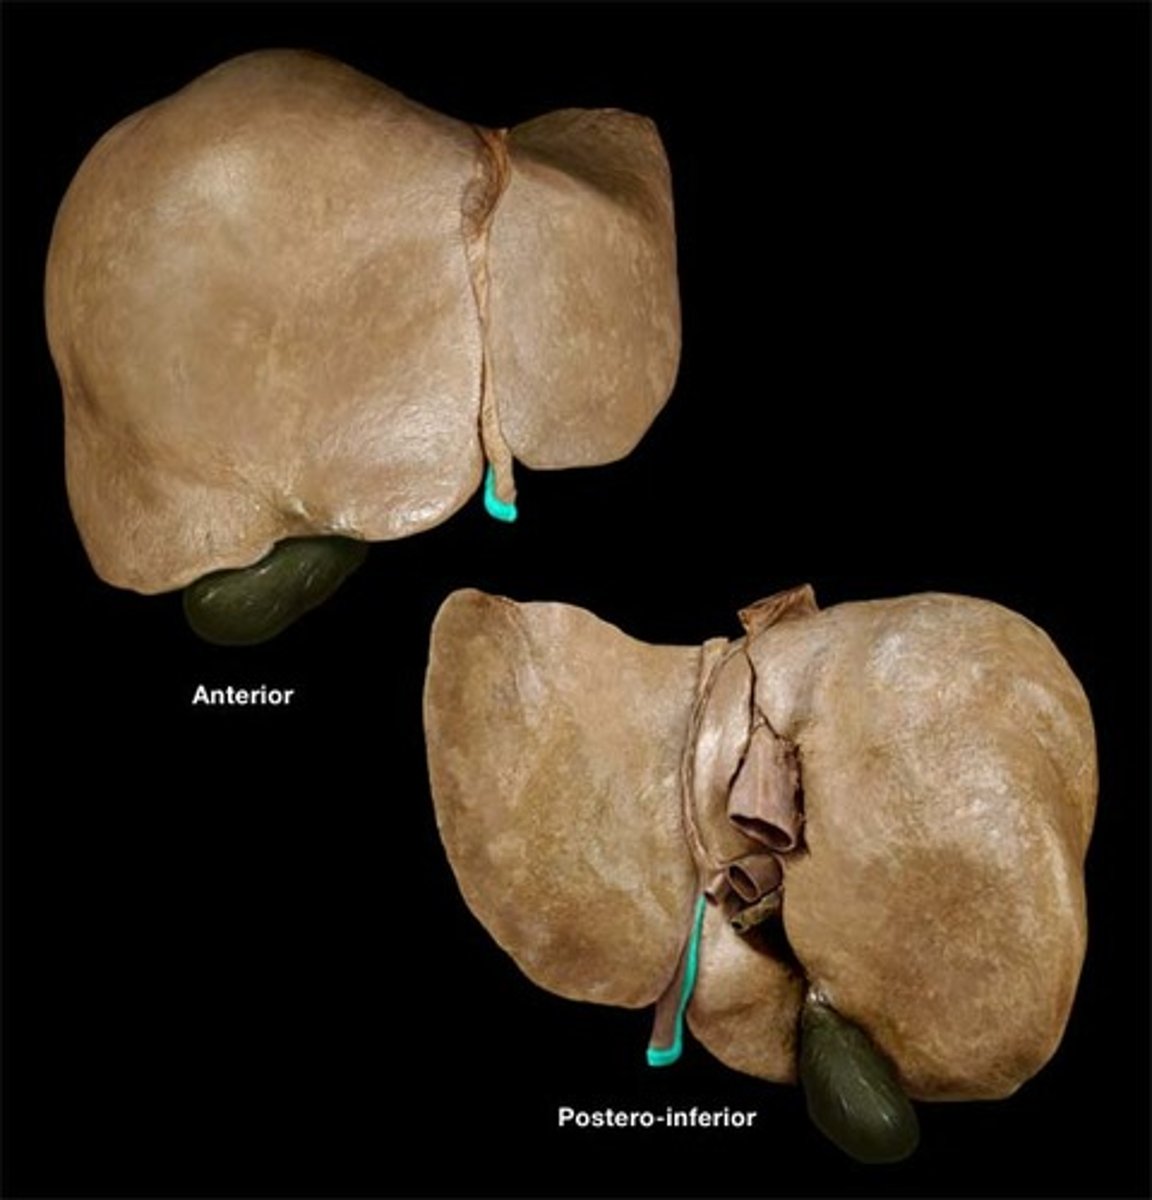

right lobe (of liver)

left lobe (of liver)

quadrate lobe (of liver)

caudate lobe (of liver)

diaphragmatic surface (of liver)

bare area (of liver)

not covered by peritoneum

inferior vena cava

round ligament of liver

porta hepatis

where the blood and lymph vessels, bile ducts, and nerves enter and leave the liver

gallbladder

fundus (gallbladder)

body (gallbladder)

neck (gallbladder)